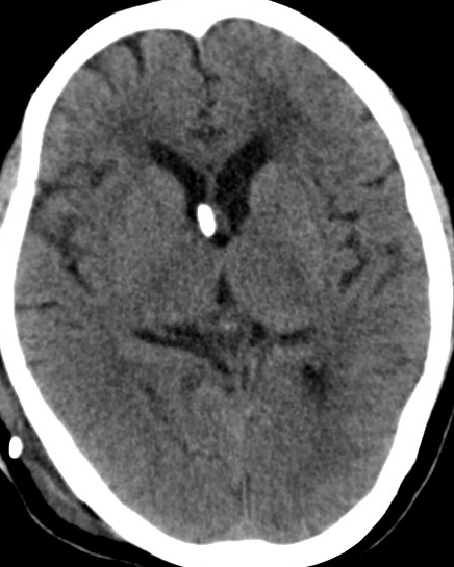

2013-8-8 CT

2013-8-12 CT